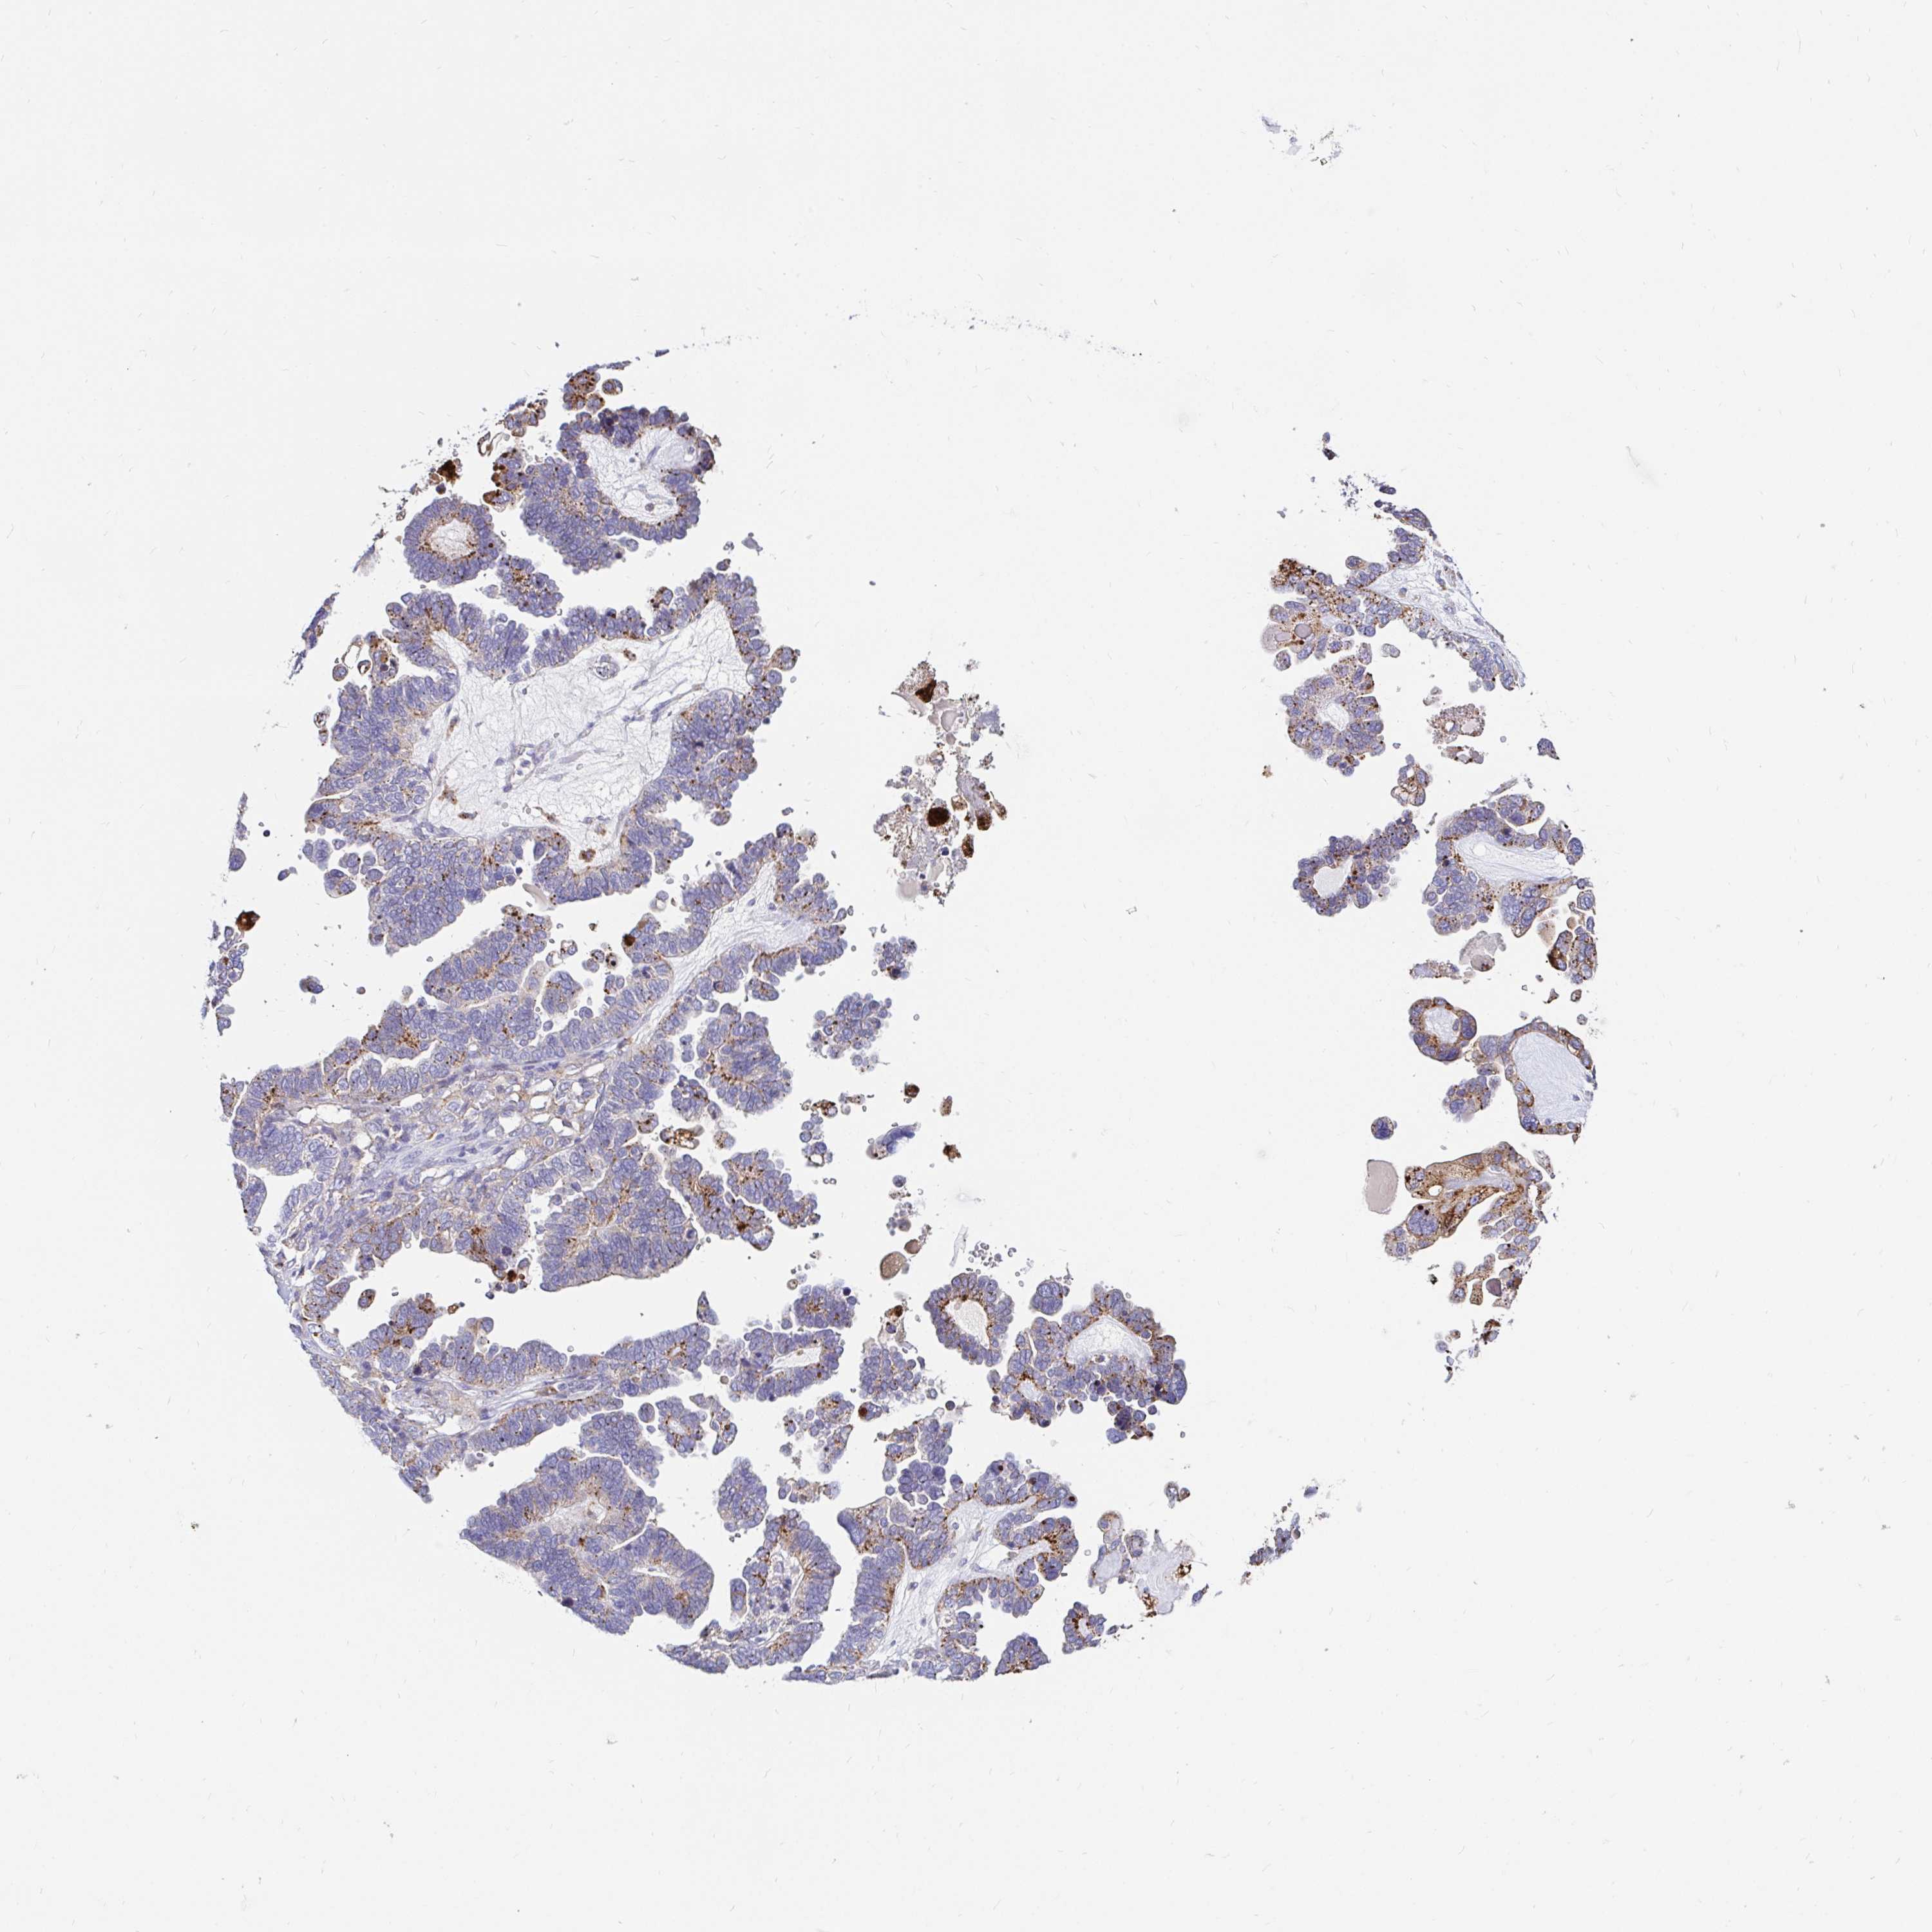

OVARIAN CANCER - Protein expressioni

A mouse-over function shows sample information and annotation data. Click on an image to view it in a full screen mode. Samples can be filtered based on level of antibody staining by selecting one or several of the following categories: high, medium, low and not detected. The assay and annotation is described here.

Note that samples used for immunohistochemistry by the Human Protein Atlas do not correspond to samples in the TCGA dataset.

Antibody stainingi

Antibody staining in the annotated cell types in the current human tissue is reported as not detected, low, medium, or high, based on conventional immunohistochemistry profiling in selected tissues. This score is based on the combination of the staining intensity and fraction of stained cells.

Each image is clickable and will lead to virtual microscopy that enables deeper exploration of all samples and also displays staining intensity scores, fraction scores and subcellular localization as well as patient and tissue information for each sample.

Antibody HPA046542

Antibody HPA056371

Staining

High

Medium

Low

Not detected

Intensity

Strong

Moderate

Weak

Negative

Quantity

>75%

75%-25%

<25%

None

Location

Nuclear

Cytoplasmic/membranous

Cytoplasmic/membranous,nuclear

Cystadenocarcinoma, serous, NOS

Carcinoma, NOS

Cystadenocarcinoma, mucinous, NOS

Carcinoma, endometroid